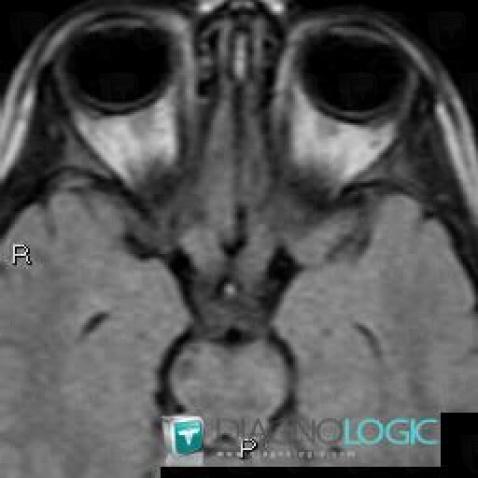

Neurofibromatose, OEil, IRM

Voici les informations spécifiques à l'image clé ci dessus:

- Diagnostic Neurofibromatose, Localisation(s) Oeil, comportant les gammes

- Diagnostic Gliome du nerf optique , Localisation(s) Nerf optique, comportant les gammes Lésion du nerf optique